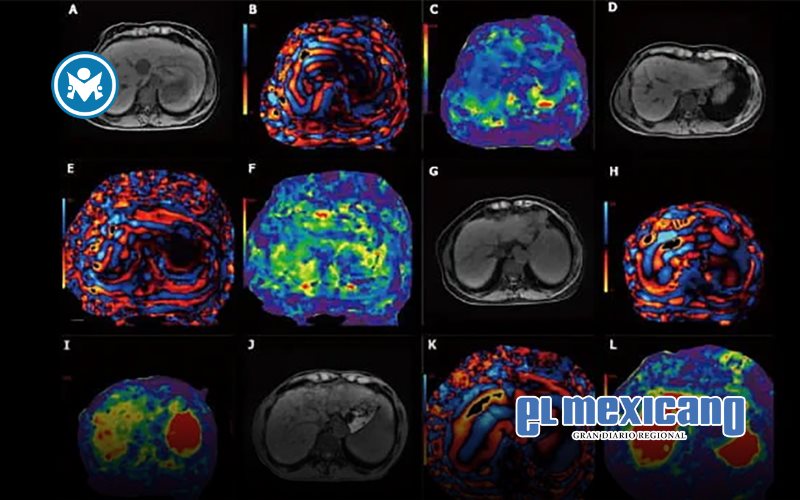

A diferencia de una resonancia magnética abdominal completa, que captura una amplia gama de estructuras abdominales y suele requerir el uso de medio de contraste, el hepatograma MASLD se enfoca únicamente en el contenido de grasa y la rigidez del hígado. Para ello, se apoya en dos técnicas clave: la cuantificación de grasa por resonancia magnética y la elastografía por resonancia magnética, que utiliza ondas mecánicas suaves para medir la rigidez hepática, un indicador directo de fibrosis.

"Es, esencialmente, un examen diseñado a la medida", comenta el Dr. Nakul Gupta, radiólogo diagnóstico en el Hospital Houston Methodist, quien desarrolló el nuevo protocolo junto al Dr. Victor. "Lo redujimos a las secuencias esenciales que responden a una pregunta muy específica: ¿este paciente padece o no fibrosis hepática esteatósica?".